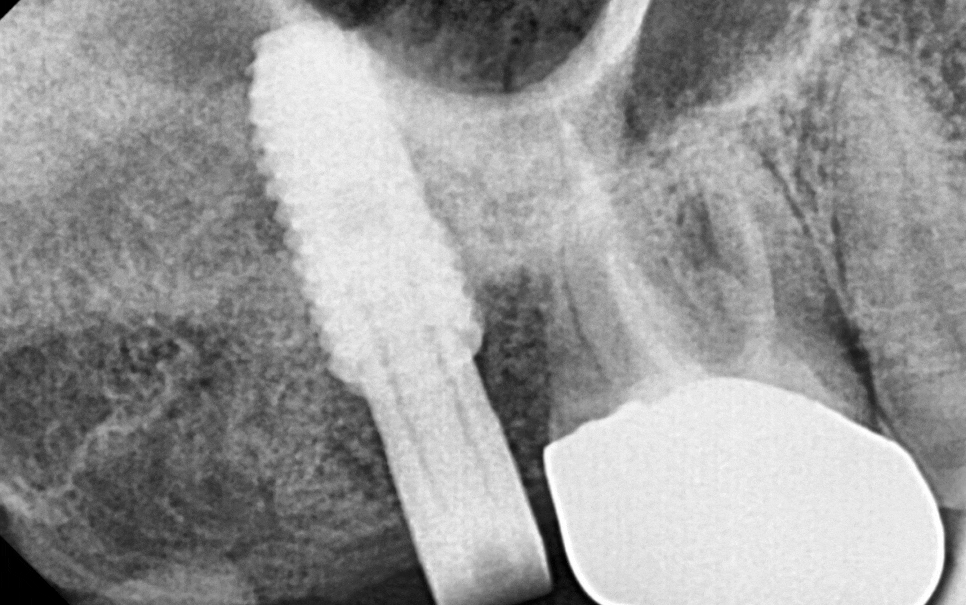

동그랗게 뼈가 올라간 것이

잘 보이시죠~?